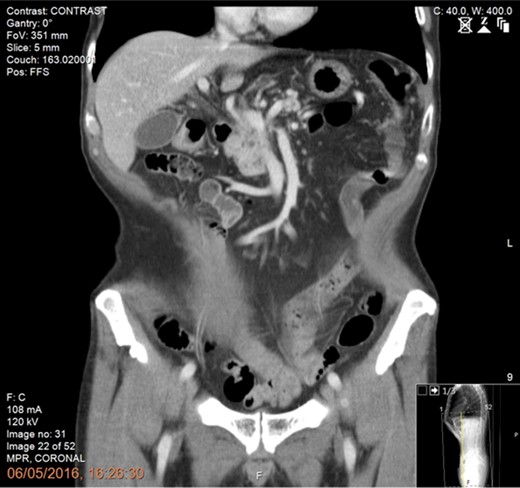

Following tissue confirmation, the patient was treated with neoadjuvant chemotherapy including 12 cycles of FOLFIRINOX. Re-staging CT scan showed good response with a recanalized portal vein without any evidence of vascular involvement or distant metastasis (Fig. 2). The patient was then offered a pancreaticoduodenectomy (PD) with simultaneous intraoperative IRE margin accentuation.

Preoperative CT scan of the abdomen and pelvis (portal phase) showing good response following neoadjuvant chemotherapy with recanalization of the portal vein and no evidence of vascular involvement or distant metastasis.